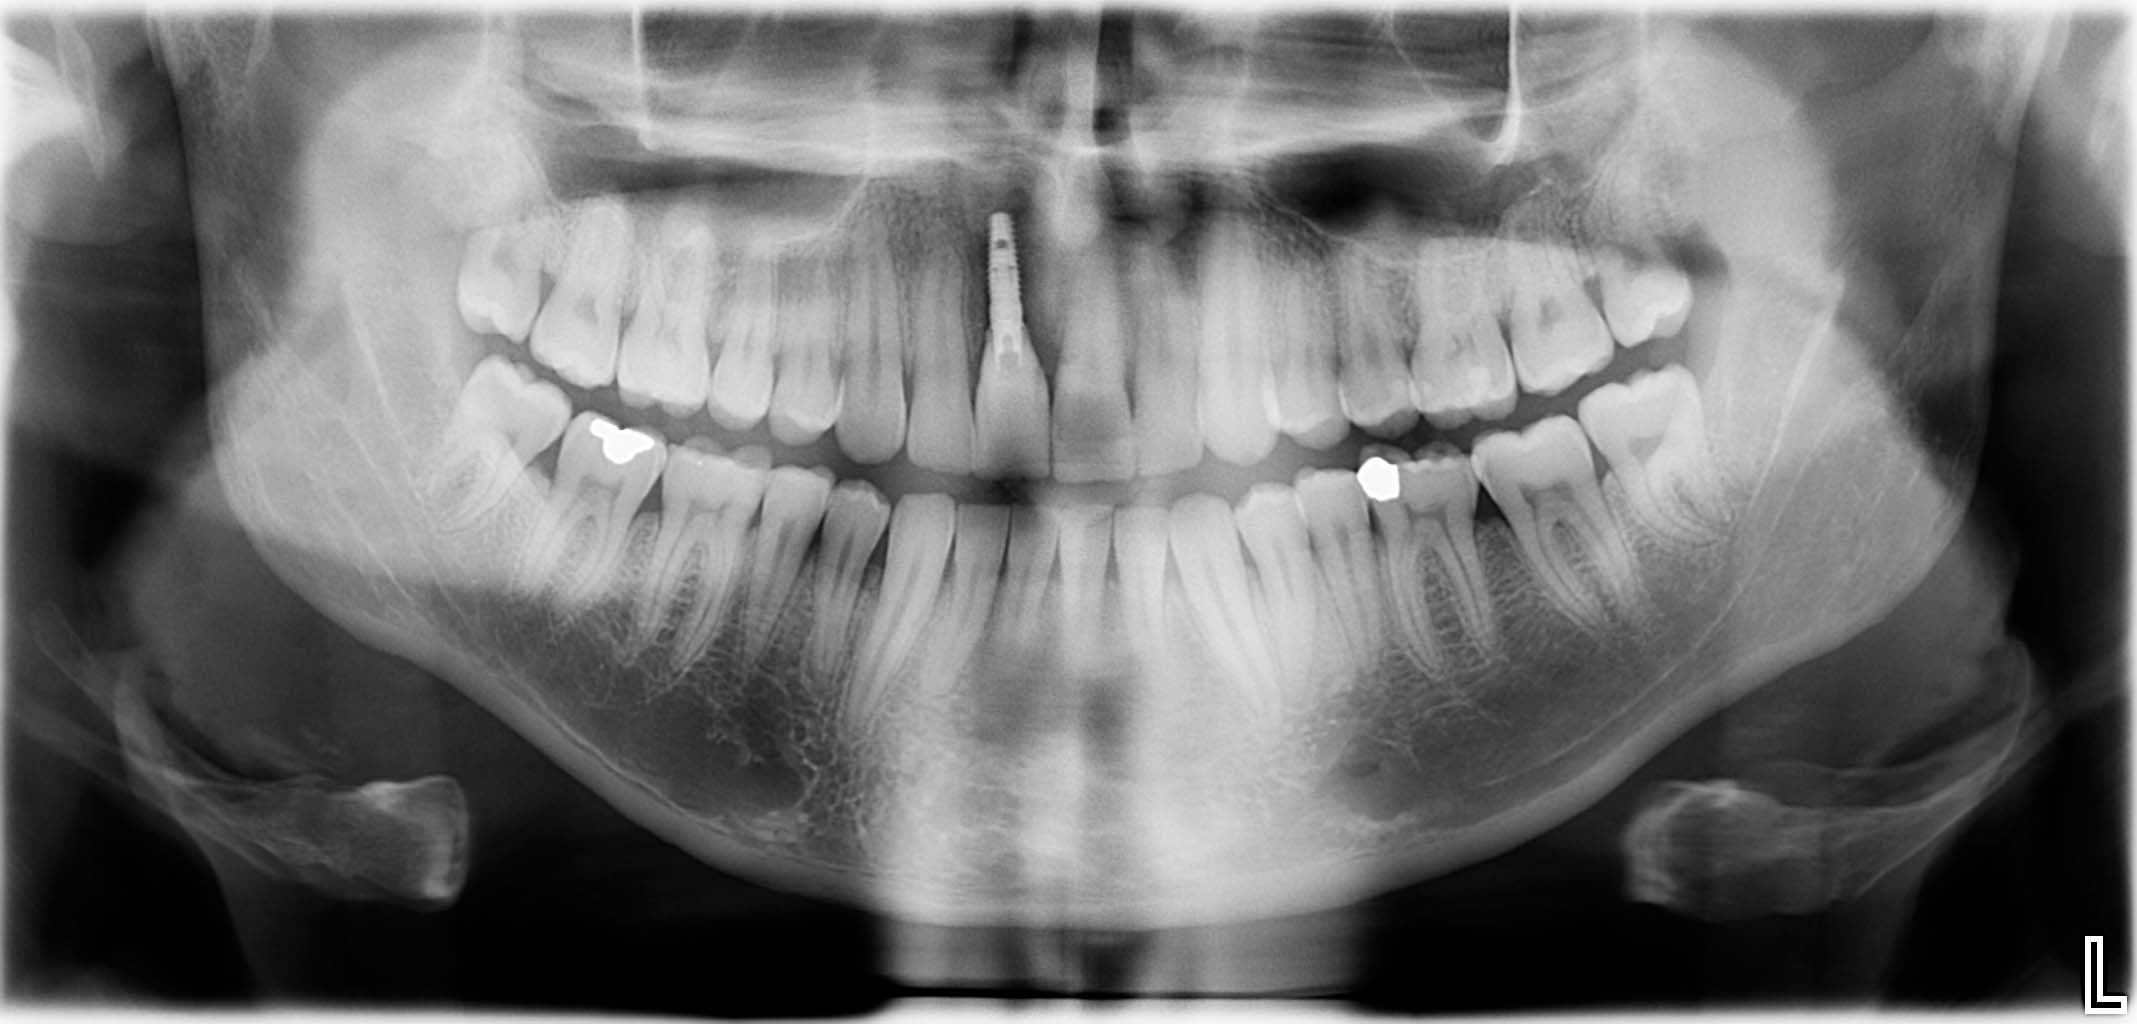

Ausgangssituation: Zahn 36 mit apikaler Beherdung, nicht erhaltungswürdig